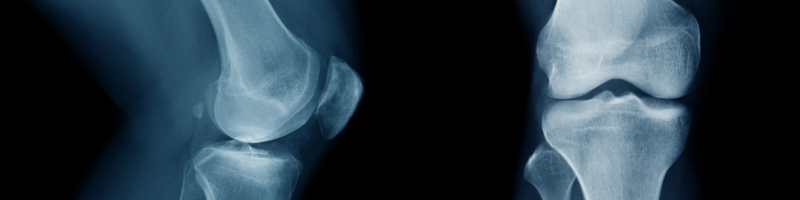

A patela é um osso pequeno e triangular localizado na parte anterior do joelho, responsável por proteger a articulação e auxiliar no movimento de extensão da perna. Ela desliza sobre o fêmur durante movimentos como caminhar, subir escadas, agachar ou correr.

Na condromalácia patelar, ocorre uma degeneração progressiva da cartilagem que reveste a parte posterior da patela. Essa cartilagem tem a função de reduzir o atrito entre os ossos, permitindo movimentos suaves e sem dor. Quando ela se desgasta, o contato entre as superfícies articulares torna-se irregular, gerando inflamação, desconforto e dor.